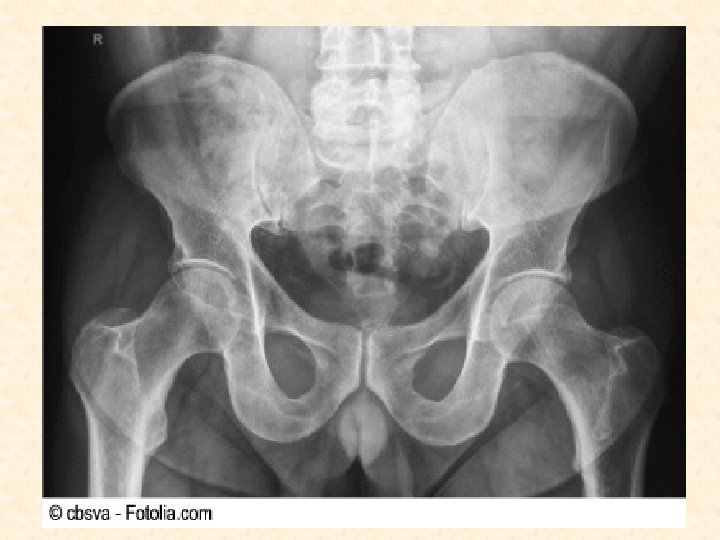

D. TÉCNICAS DE IMAGEN DEL CUERPO VIVO a. Radiología convencional: - Se utiliza una energía (radiación) que interaccione con el objeto y posteriormente se recoge en un receptor adecuado (placa radiográfica). - Por este procedimiento se obtiene una representación bidimensional de un objeto tridimensional en la que se superponen todas las estructuras atravesadas por la radiación.